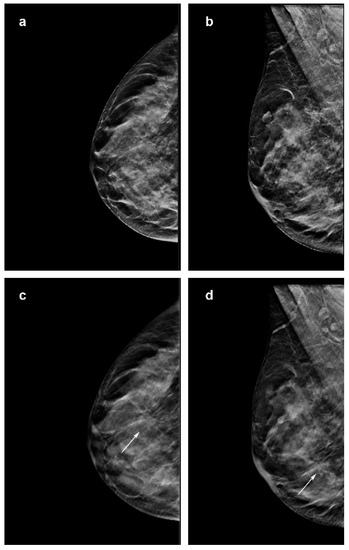

Figure 4.

Images of a 65-year-woman with a 38 mm, spiculated and palpable mass (arrow in a–d) in the upper central quadrant of the left breast detected at screening with digital breast tomosynthesis (DBT) plus synthetic mammography (synt2D). Mass was invasive lobular carcinoma. (c) Image from single-slice DBT in craniocaudal view. (d) Single-slice DBT image in mediolateral oblique view. (a) Image from synt2D in craniocaudal view. (b) Image in mediolateral oblique synt2D view. The mass is easily identifiable in synt2D and DBT, but DBT (c,d) increases the contrast, emphasizing the presence of spicules, and resulting in a better estimate of size.

As shown by the literature, our study confirmed that DBT could increase the conspicuity of ILC (Figure 3). In fact, 4/78 lesions were not recognized using only synt2D and were recovered by all breast dedicated readers only in DBT. Moreover, 18 to 27% of cases were recovered with DBT by at least one reader. Our data indicate that DBT increases detection of lobular breast cancer compared with synt2D: ILCs were more likely to have high conspicuity at DBT than at synt2D for each reader (Figure 5).

Other investigations reported that ILC is commonly presented as a mass on mammography. Of note, in our series 10/50 opacities were not recognized by at least one reader at synt2D but were visualized by all the readers at DBT. Two out of ten tumors with small diameter were identified in fatty breast only at DBT by all the readers (Figure 2). This could be explained by the better capabilities of DBT than synt2D in the evaluation of spiculated or ill-defined masses (Figure 3). Our results confirmed that calcifications with or without opacity due to their high density are easy to detect on both synt2D and DBT.